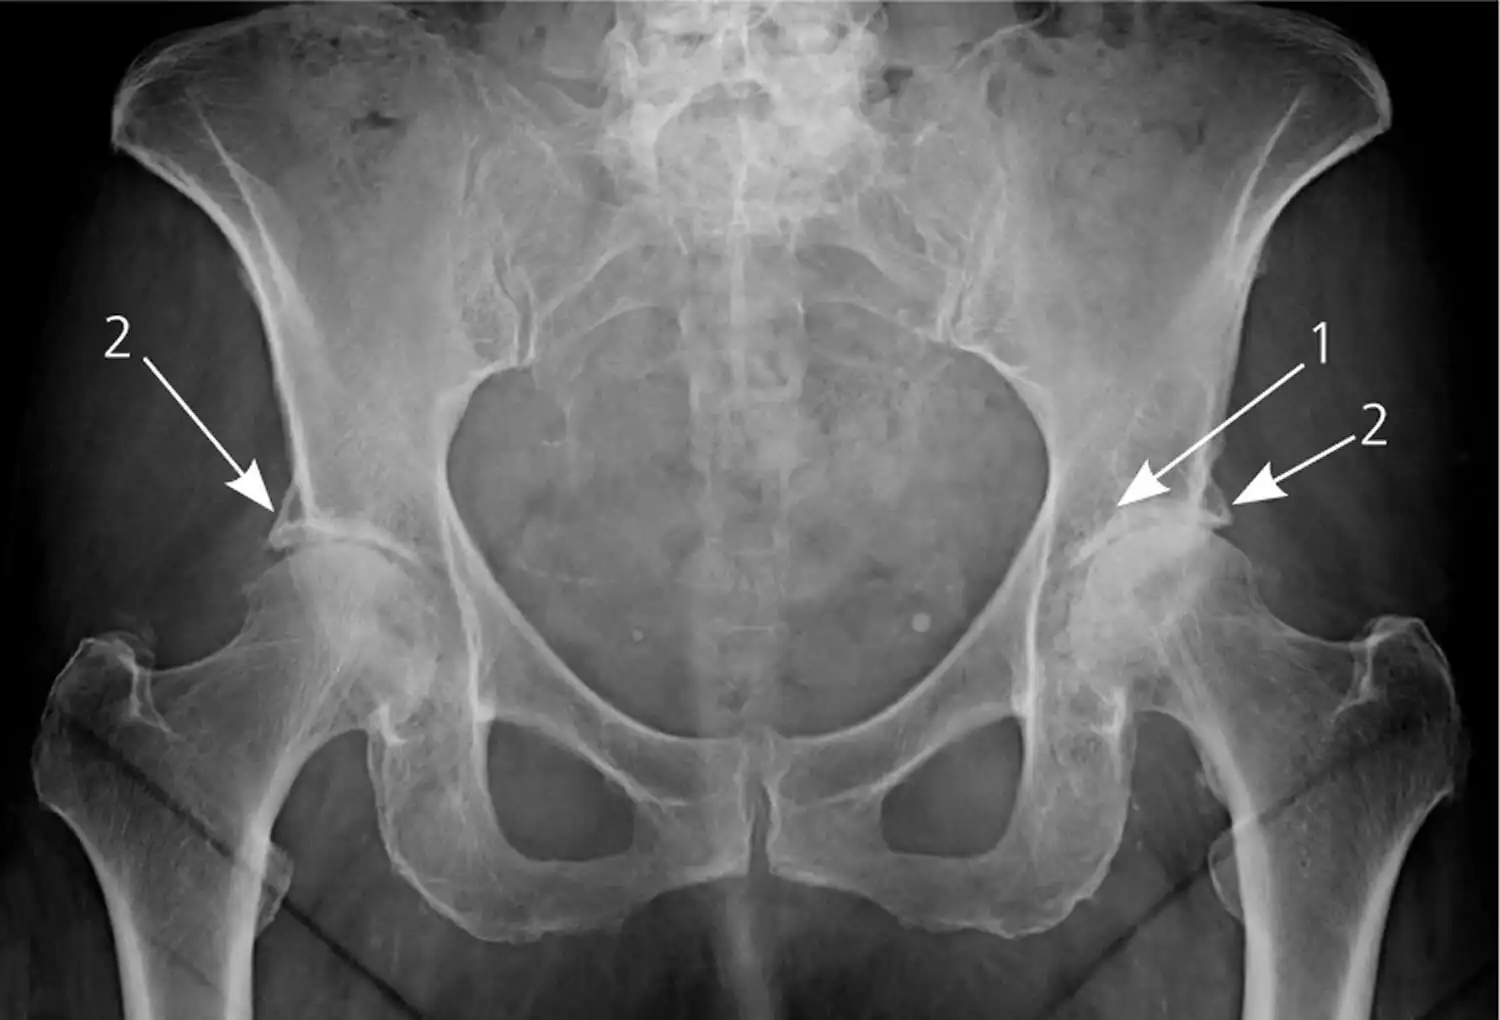

تغییرات دژنراتیو زانو چیست

تغییرات دژنراتیو زانو شامل ساییدگی و تحلیل رفتن تدریجی غضروف مفصلی زانو است. این تغییرات میتوانند ناشی از عوامل مختلفی از جمله افزایش سن، آسیبهای وارده به زانو، چاقی مفرط، ضعف عضلات اطراف زانو و زمینههای ژنتیکی باشند. با تحلیل رفتن غضروف، استخوانهای ران و ساق پا در معرض ساییدگی مستقیم قرار میگیرند که این امر منجر به التهاب، درد، خشکی مفصل و کاهش دامنهی حرکات زانو میشود.

- شیوع آرتروز با افزایش سن، به طوری که حدود نیمی از افراد بالای 65 سال شواهدی از آرتروز زانو در رادیوگرافی نشان می دهند. (منبع: National Institute of Arthritis and Musculoskeletal and Skin Diseases (NIAMS))